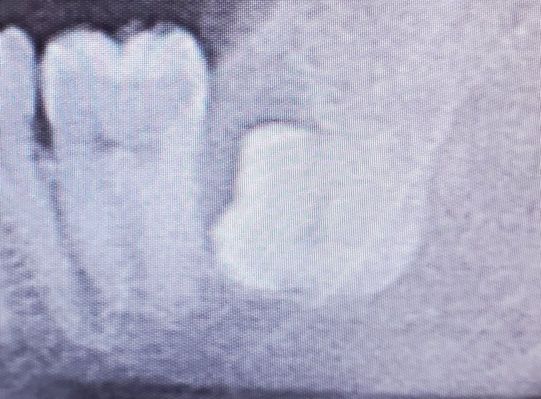

下顎の低位水平埋伏智歯

実際の下あごの横に倒れている親知らずの抜歯の順序

③周囲の骨を一部ドリルで削除してからおやしらずの頭の部分をドリルで切断し除去します。

④歯の頭の部分が除去できれば残りの根っこを抜歯します。